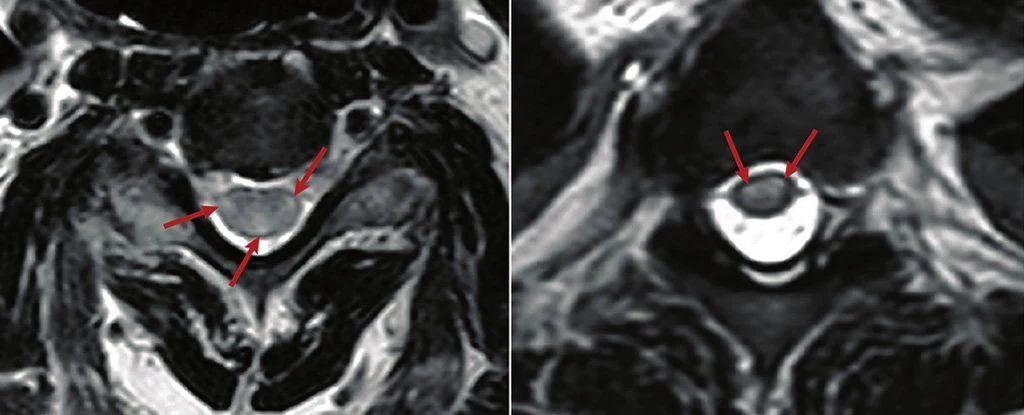

Naukowcy oficjalnie powiązali COVID-19 z rzadkim stanem neurologicznym. Mowa o ostrym poprzecznym zapaleniu rdzenia kręgowego (ATM).

Ostre poprzeczne zapalenie rdzenia kręgowego (ATM) to zapalenie rdzenia kręgowego, które może powodować ból, paraliż i problemy sensoryczne. Zostało ono zidentyfikowane u 43 dorosłych z COVID-19 w 21 krajach, z wiekiem pacjentów od 21 do 73 lat, a także u trojga dzieci, w wieku od 3 do 14 lat.

Rocznie częstość występowania ATM szacuje się na zaledwie 1,34-4,6 przypadków na milion osób. Dla porównania, w ciągu ostatnich 10 miesięcy, częstość występowania ATM wśród samych pacjentów z COVID-19 wyniosła ok. 0,5 na milion, co stanowiło dla uczonych sygnał alarmowy."Stwierdziliśmy, że ATM jest niespodziewanie częstym neurologicznym powikłaniem COVID-19. Większość przypadków (68 proc.) miała latencję od 10 dni do 6 tygodni, co może wskazywać na poinfekcyjne powikłania neurologiczne, w których pośredniczy odpowiedź gospodarza na wirusa" - czytamy w badaniu koordynowanym przez Neurological Institute w Houston Methodist Hospital.Już wcześniej stwierdzono, że COVID-19 wywołuje liczne problemy związane z układem nerwowym, m.in. utrzymujący się efekt "mgły mózgowej". W 43 potwierdzonych przypadkach ATM stwierdzono, że uszkodzenia rdzenia kręgowego prowadzą do czterokończynowego porażenia mózgowego i paraplegii, m.in. z utratą kontroli nad pęcherzem. Wszystkie badane przypadki zarejestrowano między marcem 2020 r. a stycznie 2021 r."Ten przegląd potwierdza, że ATM nie jest rzadkością jako powikłanie neurologiczne związane z infekcją COVID-19 na całym świecie, odpowiedzialne być może za 1,2 proc. wszystkich powikłań neurologicznych spowodowanych przez koronawirusa" - czytamy w raporcie.ATM jest stanem uwarunkowanym immunologicznie, więc istnieją pewne potencjalne mechanizmy odpornościowe, które mogłyby wyjaśnić, w jaki sposób SARS-CoV-2 może prowadzić do ATM. Ponadto, naukowcy zauważyli również, że trzy przypadki ATM wystąpiły w badaniach szczepionki AstraZeneca. Chociaż każdy z nich był osobno analizowany, mogą one dostarczyć wskazówek co do zaangażowanych mechanizmów immunologicznych."Patogeneza ATM pozostaje nieznana, ale można przypuszczać, że antygeny SARS-CoV-2, być może obecne również w szczepionce AZD1222 COVID-19 lub jej adiuwancie z adenowirusem szympansa, mogą indukować mechanizmy immunologiczne prowadzące do zapalenia rdzenia" - wynika z raportu.Wyniki zostały opublikowane we "Frontiers in Immunology".